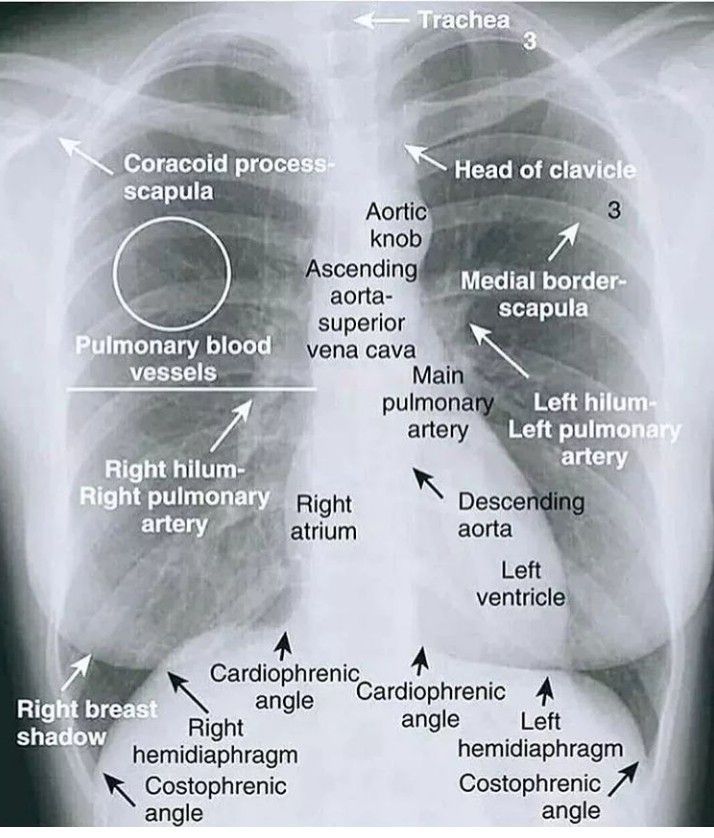

Chest X-ray Interpretation

An easy interpretation of chest X-ray is shown here.